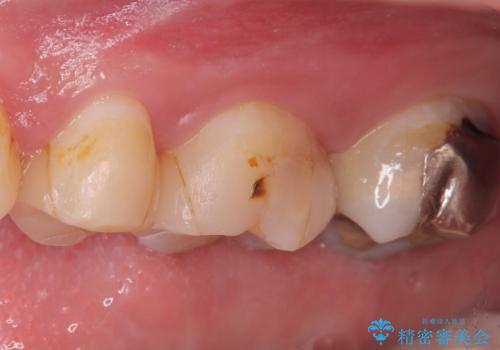

【セラミッククラウン】インレーの下の大きな虫歯

- レントゲンにて昔入れたインレーの下に虫歯が見つかった患者様です。

歯髄に近接する虫歯でしたが、根管治療は必要なくクラウンにて修復を行うことができました。